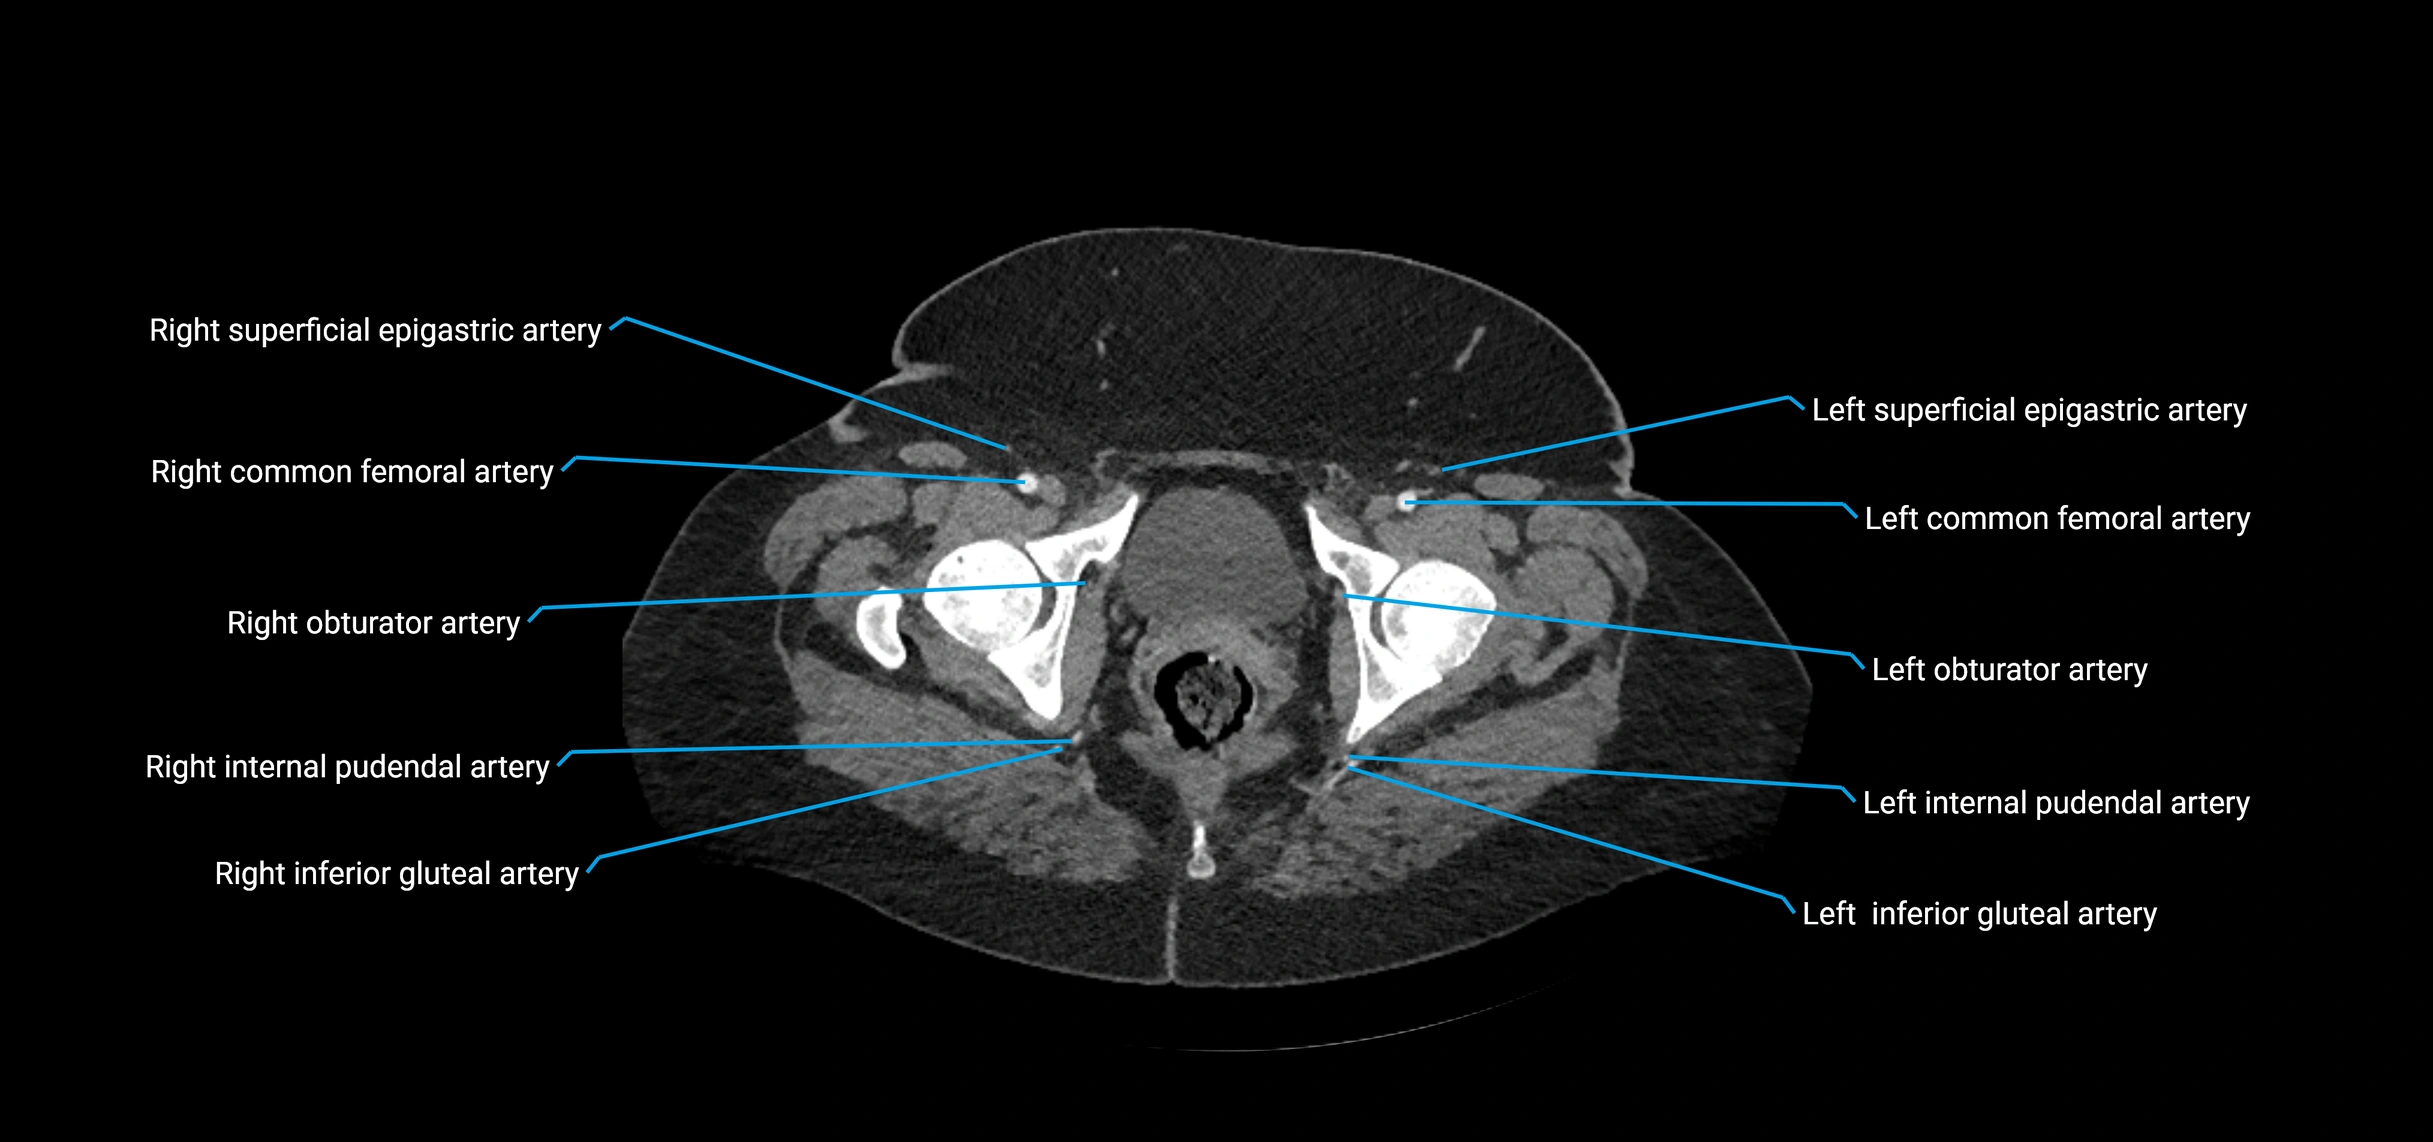

Contrast-enhanced CT (CTA):

• Gold standard for abdominal aortic imaging

• Provides excellent detail of lumen, wall, aneurysm, thrombus, and branch vessels

• Multiplanar and 3D reconstructions help in aneurysm measurement, stent graft planning, and dissection evaluation

• Detects acute rupture, traumatic injury, or occlusion with high sensitivity